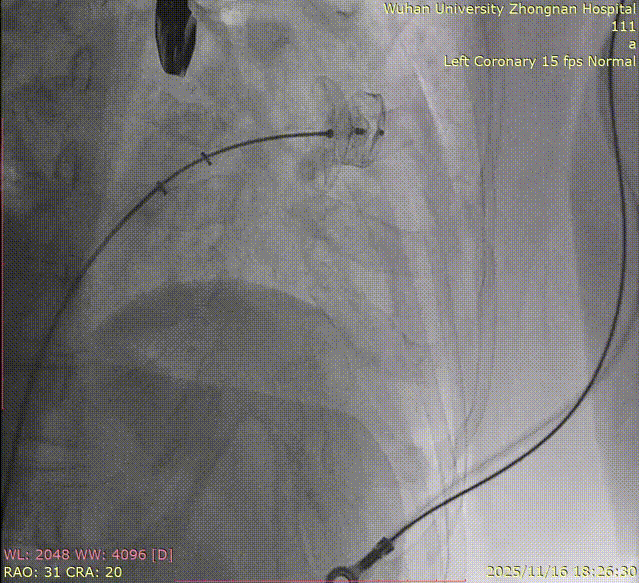

K-Clip® Tricuspid Annuloplasty (Seamless Transition):Immediately after LAAC, the operators established a new vascular access route and advanced the K-Clip® delivery system directly into the right atrium, targeting the posterior-septal and anterior-posterior commissures of the tricuspid annulus. Under real-time ultrasound guidance, the team precisely anchored, clipped, and released the devices.

2.Advancement of the steerable large sheath and delivery system under ultrasound guidance.

3.Steering and rotating the delivery system to target the site while engaging the anchor screw via the 3D MPR plane.

4.Opening the clip arms, adjusting orientation, landing, and closing the clip.